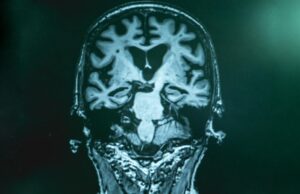

Η παχυσαρκία μπορεί να επιταχύνει την εμφάνιση του Αλτσχάιμερ, λένε επιστήμονες

Μια μικρή μελέτη δείχνει ότι οι τακτικές εξετάσεις αίματος μπορεί να είναι χρήσιμη συμπλήρωση στις σαρώσεις εγκεφάλου που καταγράφουν την πρόοδο της νόσου Αλτσχάιμερ.